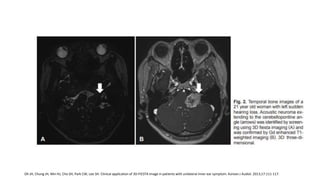

RM

Sensibilidad del 100%

• Gold estándar: T1 realce con contrate.

• Imágenes ponderadas en T2

• CISS o FIESTA

RM Sensibilidad del 100% •Gold estándar: T1 realce con contrate. • Imágenes ponderadas en T2 • CISS o FIESTA Abele TA, Besachio DA, Quigley EP, et al. Diagnostic accuracy of screening MR imaging using unenhanced axial CISS and coronal T2WI for detection of small internal auditory canal lesions. Am J Neuroradiol. 2014;35:2366-2370. Oh JH, Chung JH, Min HJ, Cho SH, Park CW, Lee SH. Clinical application of 3D-FIESTA image in patients with unilateral inner ear symptom. Korean J Audiol. 2013;17:111-117. American Academy of Otolaryngology–Head and Neck Surgery. Clinical Practice Guideline: Sudden Hearing Loss (Update). Otolaryngology– Head and Neck Surgery 2019, Vol. 161(1S) S1–S45 Cadoni G, Cianfoni A, Agostino S, et al. Magnetic resonance imaging findings in sudden sensorineural hearing loss. J Otolaryngol. 2006;35:310-316.

• FIESTA Sensibilidad: 84.6%-98% Especificidad:96-100% IC 95% interobservador Ordóñez L. VALIDACIÓN DE UNA PRUEBA DIAGNÓSTICA: SECUENCIA FIESTA DE IMÁGENES DE RESONANCIA MAGNÉTICA EN SCHWANOMA VESTIBULAR. Rev.Medica.Sanitas 15 (4): 18-25, 2012